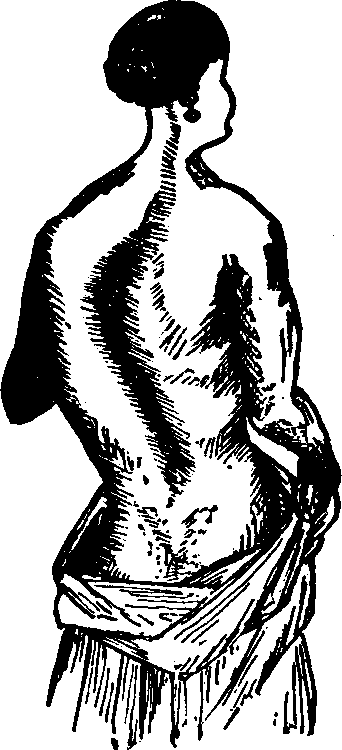

Symptoms. The sufferer from leucorrhea becomes pale and emaciated, the eyes dull and heavy, the functions of the skin, stomach and bowels become deranged, more or less pain in the head is experienced, sometimes accompanied with dizziness, palpitation is common, and, as the disease progresses, the blood becomes impoverished, the feet and ankles are swollen, the mind is apprehensive and melancholy, and very frequently the function of generation is injured, resulting in complete sterility. Exercise produces pain in the small of the back and the lower portion of the spine, and, owing to a relation of the vaginal walls, the womb falls far below its natural position, or turns in various directions, according to the manner in which the weight above rests upon it. Ulcers are apt to appear upon the mouth of the womb, the matter from which tinges the discharge and stains the linen. Hysteria is often an attendant of this disease.